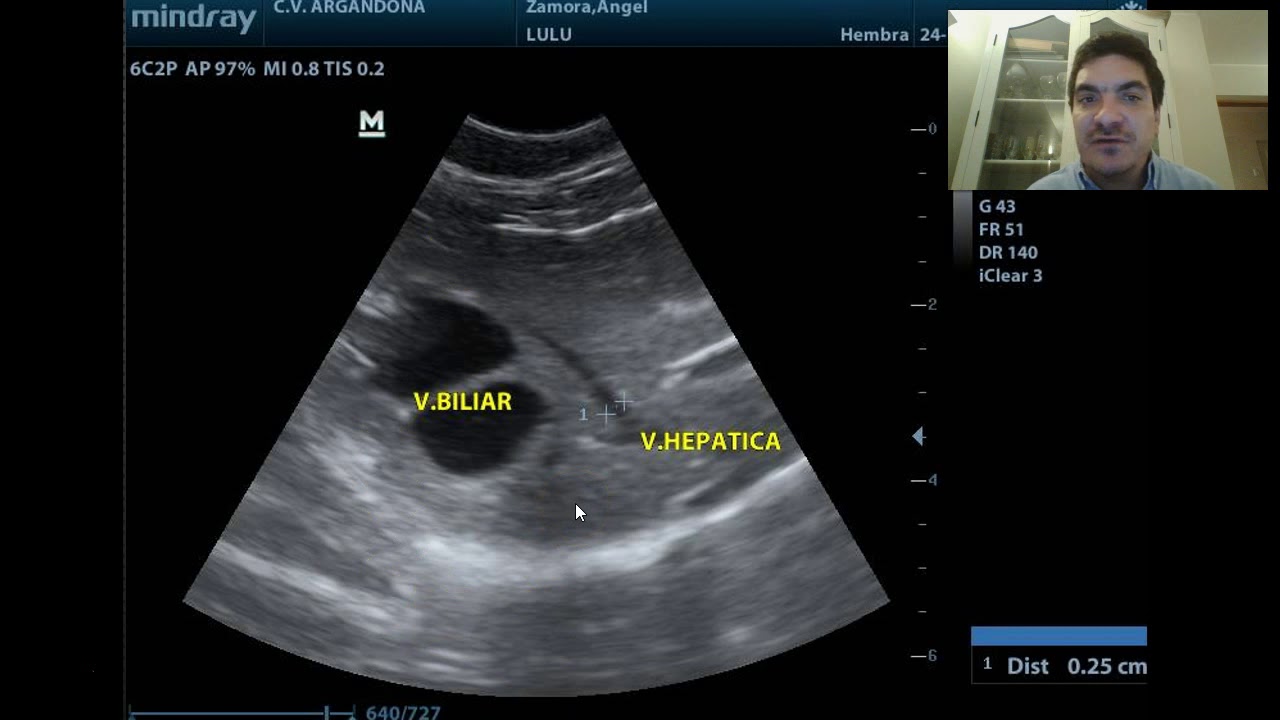

Ecografía abdominal parte 3

Автор: Enrique Argandoña Rojas

Описание: es la continuación y término de la presentación de ecografía abdominal en especies menores